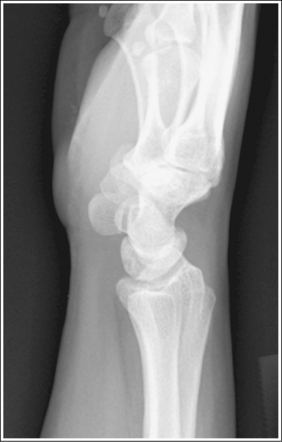

See Figure 4-36 and Box 4-13.

The wrist is in a lateral projection. The anterior aspect of the distal scaphoid and pisiform are aligned, and the radius and ulna are superimposed.

• A lateral projection of the wrist is accomplished by flexing the elbow 90 degrees and abducting the humerus until it is parallel with the IR, placing the entire arm on the same horizontal plane. Rotate the wrist into a lateral projection with its ulnar (medial) aspect against the IR (Figure 4-38). To ensure a true lateral projection, place the palmar aspect of your thumb and forefinger against the anterior and posterior aspects, respectively, of the patient's wrist joint, as shown in Figure 4-39. Adjust wrist rotation until your thumb and finger are aligned perpendicular to the IR.

• Detecting wrist rotation. The relationship between the pisiform and distal aspect of the scaphoid can best be used to discern whether a lateral wrist projection has been obtained. On a lateral projection, these two carpals should be superimposed, with their anterior aspects aligned. When the wrist is rotated, the anteroposterior relationship between the distal scaphoid and pisiform changes, and the pronator fat stripe is obscured. If the anterior aspect of the distal scaphoid is positioned posterior to the anterior aspect of the pisiform, the patient's wrist was externally rotated (see Image 45). If the anterior aspect of the distal scaphoid is positioned anterior to the anterior aspect of the pisiform, the patient's wrist was internally rotated (see Images 46 and 47). A second method of determining how to reposition a rotated lateral wrist projection uses the radius and ulna. The ulna is positioned anterior to the radius when the wrist was externally rotated and the ulna is positioned posterior to the radius when the wrist was internally rotated. Because the exact amount of superimposition of the radius and ulna depends on the position of the humerus, and their poor positioning is not as sensitive, you should always view the pisiform and distal scaphoid relationship when determining whether the wrist is in a lateral projection.

The carpal bones do not indicate radial or ulnar deviation. The distal aspect of the distal scaphoid is aligned with the distal aspect of the pisiform.

• To obtain a neutral lateral wrist projection, align the long axes of the third metacarpal and the midforearm parallel with the IR. When the proximal forearm is higher or lower than the distal forearm, the wrist is radial-deviated or ulnar-deviated, respectively. In radial and ulnar deviation the distal scaphoid moves but the pisiform's position remains relatively unchanged. Radial deviation of the wrist forces the distal scaphoid to move anteriorly and proximally (Figure 4-40), causing the distal aspect of the distal scaphoid to be positioned proximal to the distal aspect of the pisiform (see Image 49). Ulnar deviation shifts the distal scaphoid posteriorly and distally (see Figure 4-40), causing the distal aspect of the distal scaphoid to be positioned distal to the distal aspect of the pisiform (see Image 50). The degree of pisiform and distal scaphoid separation is usually very small, because you would be unlikely to position a patient in maximum wrist deviation without being aware of the positioning error. To obtain optimal lateral wrist projections, however, you must learn to eliminate even small degrees of deviation.